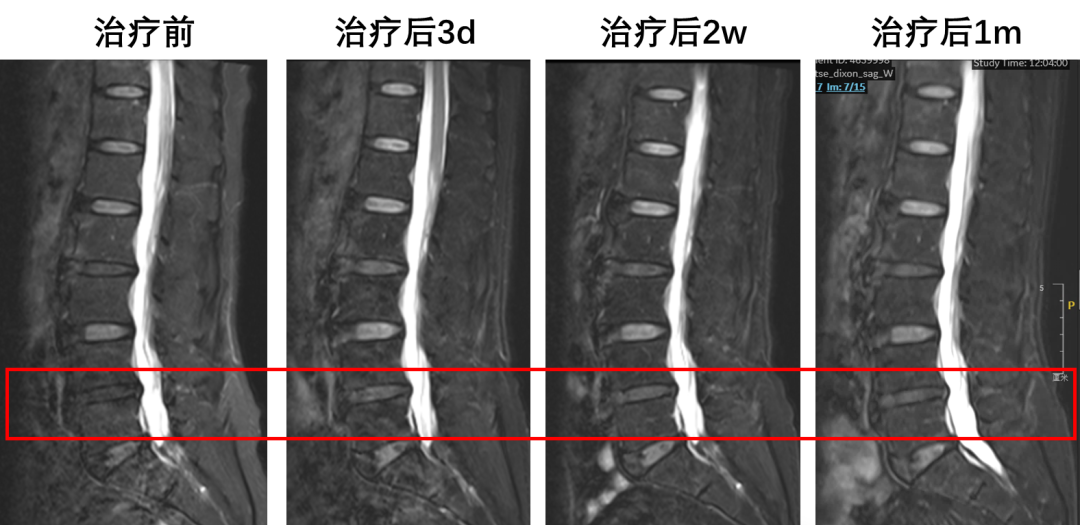

2024年9月,由赵杰教授和团队牵头开展的“FibroCell-001注射液治疗椎间盘退行性病变”的首次人体试验,顺利完成所有剂量组全部受试者给药。这款注射液的作用机制清晰而独特,堪称“双重机制,标本兼治”:

首先,抑制炎症,快速缓解症状。椎间盘内的无菌性炎症是导致腰痛的主要元凶。“安定”中的成纤维细胞具有强大的抗炎功能,从而在短时间内显著缓解患者的疼痛。

其次,促进修复,长期维稳。通过分泌胶原蛋白等物质,促进椎间盘的纤维性修复,维持其结构和高度的稳定,从而避免因椎间盘塌陷导致的神经压迫,达到长期缓解的效果。

首位接受临床研究(IIT)试验的是一位60多岁的农村女性,长年被慢性腰痛折磨。在接受单次经皮穿刺注射治疗后,短短三天,疼痛就明显缓解。如今,该患者已完成超过一年半的随访,“效果非常稳定,期间再未使用止痛药,甚至偶尔还能下地干点农活。”